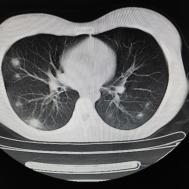

支原体肺炎1例CT影像表现

性别:女,年龄:26岁,低热,轻微胸痛,支原体阳性

两肺内及胸膜下多发斑片状高密度影,部分病灶密度较淡,部分实变,边缘可见渗出改变。

支原体肺炎是由支原体引起的以间质改变为主的肺炎。实验室检查支原体抗体呈阳性。支原体侵入肺内可引起支气管、细支气管黏膜及其周围间质充血、水肿,多核细胞浸润,侵入肺泡可产生肺泡浆液性渗出性炎症。CT早期主要改变为肺间质炎症,病变区肺纹理增粗而模糊,病变范围广泛,常累及多个肺叶,单侧或双侧的磨玻璃影及实变影,以双肺下叶多见,多呈小叶性分布。同时,患者的临床症状与CT改变不匹配,即临床症状明显好转或消失但肺部阴影吸收不明显。鉴别诊断:支气管肺炎好发于两中下肺的内、中带,病灶沿支气管分布,呈多发散在小的斑片状影,常合并阻塞性小叶性肺气肿或小叶性肺不张,结合临床多见于婴幼儿或年老体弱者。渗出浸润为主的继发性肺结核病灶表现为结节状或呈不规则斑片状影,边缘较模糊,密度不均匀,病灶内可见小空洞。增殖性病灶密度较高,边缘清楚,病灶内或周围可见不规则钙化灶。浸润性病变常与纤维化并存,可伴有邻近支气管扩张。结核分枝杆菌检查阳性。